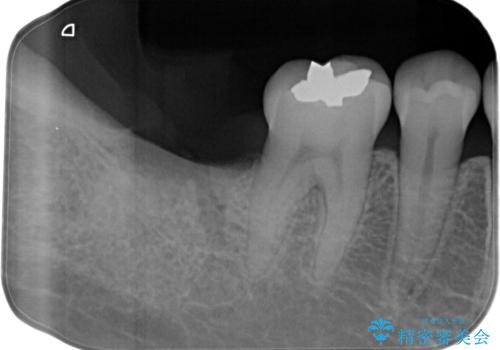

骨幅があったため、太いインプラント体を使用しています。

今回はスクリューリテインにて修復を行なっています。